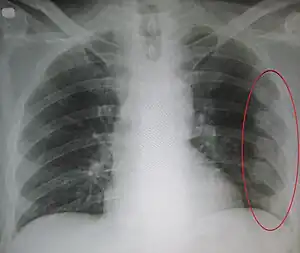

Right sided pneumothorax and rib fractures -

| An X ray showing multiple old fractured ribs of the person's left side as marked by the oval. | |